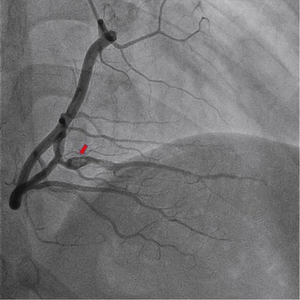

△小雷出现冠状动脉夹层。重庆市中医院供图

为探明患者病因,从而制定精准的治疗方案,心血管病科主任李勇为孩子进一步行冠状动脉介入检查,真相终于浮出水面,小雷突发胸痛,是由冠脉自发夹层导致心肌梗死。